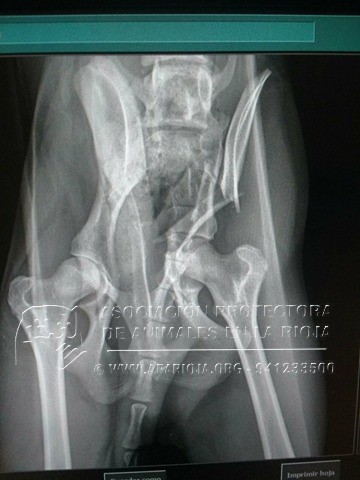

Se le estabilizó y comenzaron a aplicar los cuidados intensivos adecuados para intentar sacarle adelante. Un día después su estado mejoraba, presentaba fractura de cadera acetabular y del ala del íleon, que debían ser operadas con un coste superior a los 600€, sólo la cirugía.